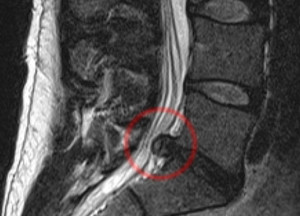

Данная патология появляется в случае разрыва позвоночного диска шейного или поясничного отдела в результате неравномерных нагрузок на позвоночник. Данное состояние вызывает боли в различных частях тела и неврологические проблемы. Пациент в итоге может остаться инвалидом. Причиной этому служит выпячивание диска, появляющееся при данном заболевании, в результате чего происходит сдавление нервов.

Грыжа поясничного отдела возникает, как правило, между позвонками поясничными L4 и L5 (четвертый и пятый позвонок), а также между пятым поясничным и первым крестцовым позвонком (L5 и S1). В области шейного отдела, как правило, грыжа образуется между позвонками S5 и S6. Если говорить о симптомах, то поражение позвонком L5 — S1 проявляется болями в коленях, лодыжке, распространяется на бедра, проявляется онемением нижних конечностей и пр. Грыжи могут наслаиваться друг на друга, а также проявляться одновременно на нескольких участках. Количество симптомов в этом случае возрастает.